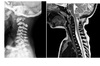

Segond fracture

Lateral tibial plateau